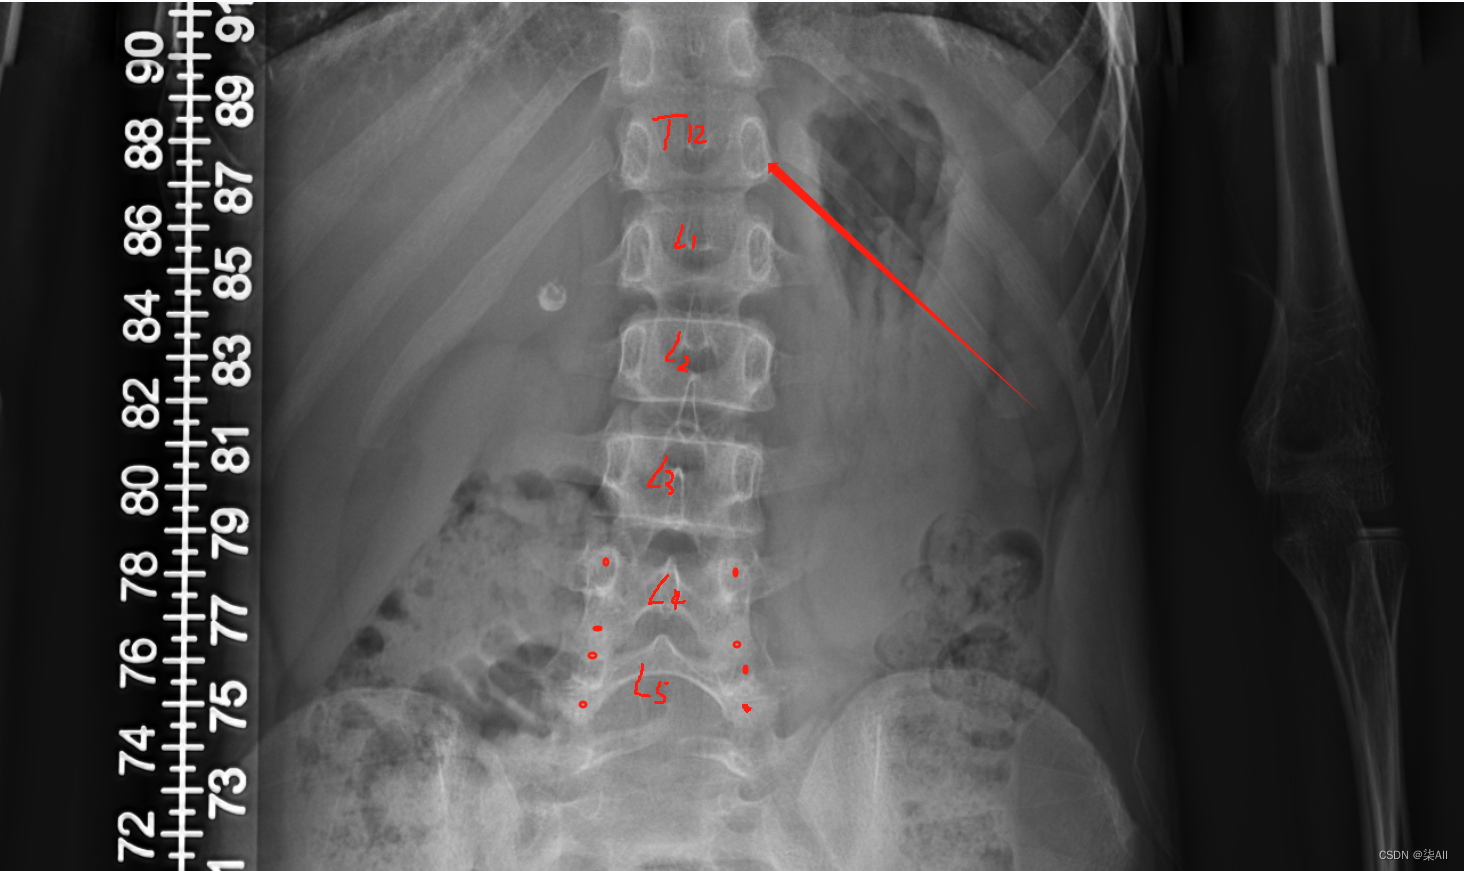

(0) 最后一个椎体看不清的话,最后一个肋骨连接的就是胸12 也就是T 12 ,下面那个就是L1(腰椎1),往下数五个就是 最后一个腰椎

- (0) 最后一个椎体看不清的话,最后一个肋骨连接的就是胸12 也就是T 12 ,下面那个就是L1(腰椎1),往下数五个就是 最后一个腰椎